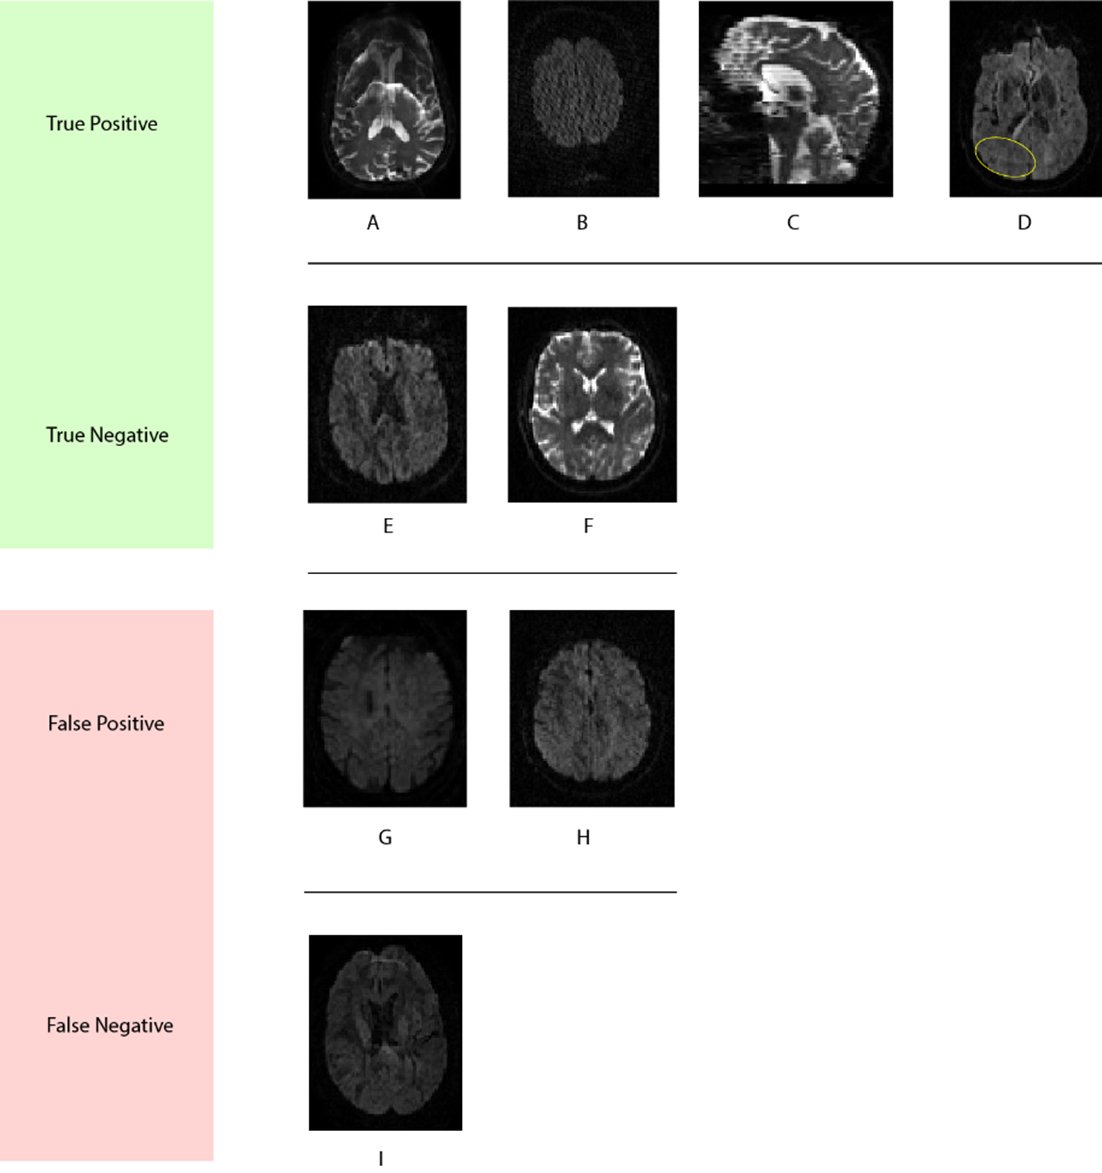

Another reason to celebrate: Adnan Ahmad will also be presenting "3D-QCNet – Automated Artifact Detection in Diffusion MRI" at the @SIIM_Tweets Conference on Machine Intelligence in Medical Imaging #CMIMI21 Way to go Adnan!🥳